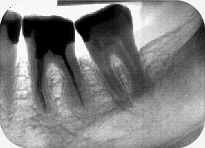

デジタルX線撮影画像で画面いっぱいに表示できる

画像が大きく表示でき、先生はより説明しやすく、また患者さんにはよりわかりやすい「インフォームドコンセント」が実現します。

現像・定着液の温度が高い場合やX線の線量が高い場合、写真は濃くなります。この例では歯槽骨のラインが消えています。

現像・定着液の温度が低い場合や液が古い場合、あるいはX線の線量が低い場合は写真が薄くなります。この例では根尖を確認することができません。

フィルタリング機能で、ぐっと見やすく、診断が容易に!